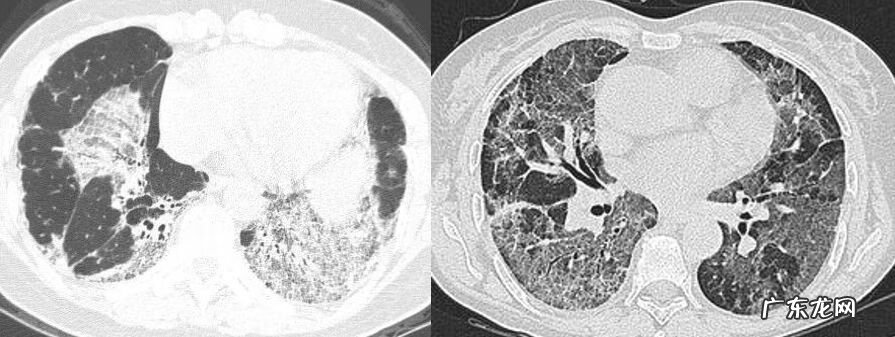

这是一位36岁的女性,咳嗽3个月,咳白色粘痰 。我们来看这个双肺下叶弥漫磨玻璃影,里边有细支气管壁增厚、牵拉、稍扩张,在胸膜下(图9) 。这是SLE继发OP,患者使用激素治疗3月,肺内病变基本吸收仅残留少许磨玻璃密度影 。

图9